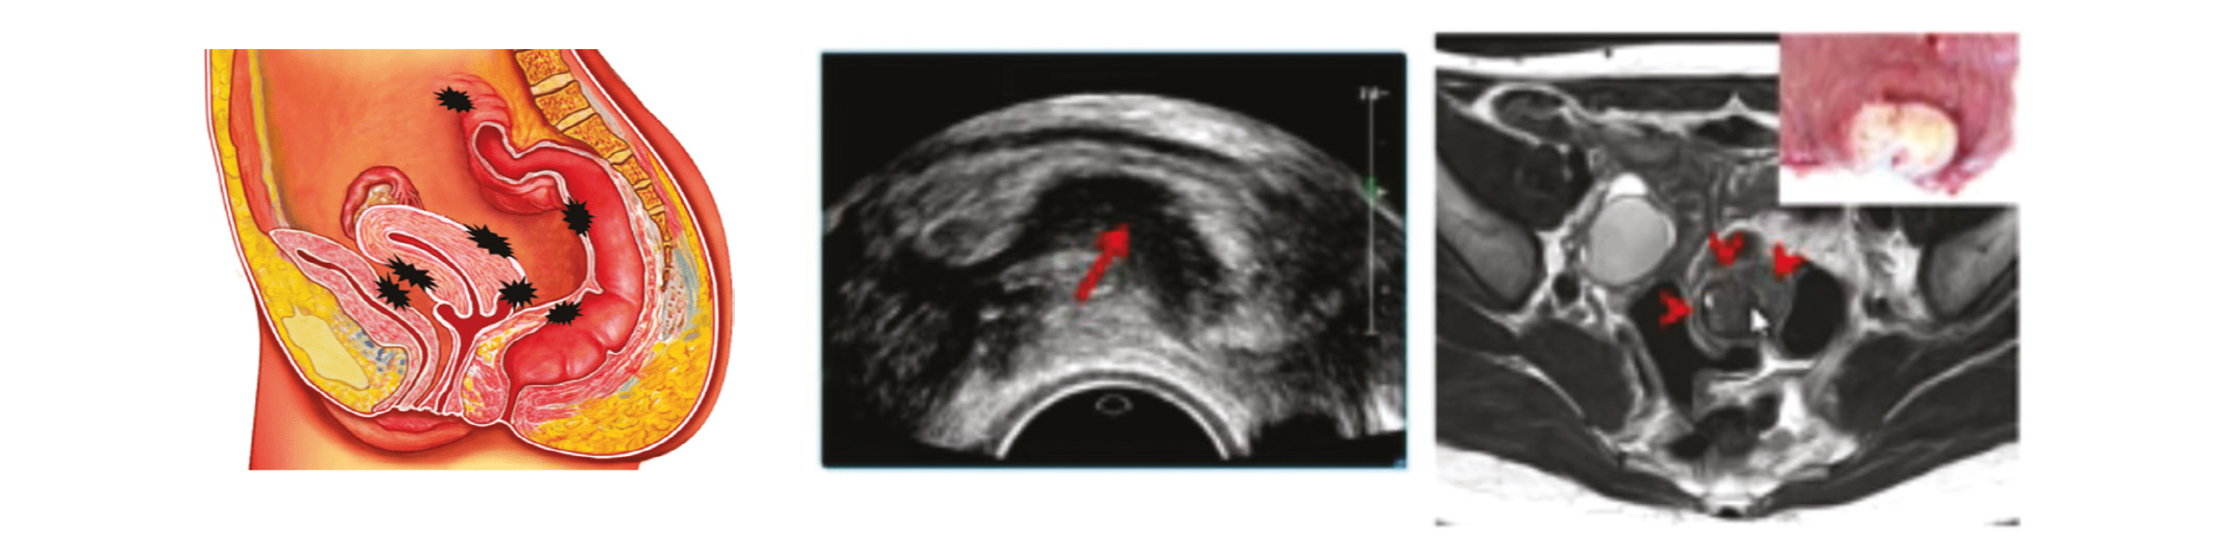

Endométriose superficielle

L'endométriose superficielle correspond à des pétéchies endométriales d'aspect polymorphes à la surface du péritoine. Le rôle du radiologue est limité, il consiste à prévenir le chirurgien si l'imagerie (IRM) est en faveur d'un pelvis adhérentiel ou s'il existe des anomalies associées comme de l'adénomyose interne ou des malformations. C'est la coelioscopie l'examen de référence.